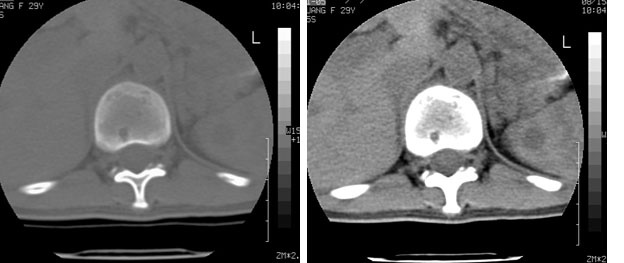

标题: CT10087:女,29岁,多发肿瘤样病变。 [打印本页]

标题: CT10087:女,29岁,多发肿瘤样病变。

车祸致t12压缩性骨折,行ct扫描意外发现椎体多发肿瘤样病变,建议加拍骨盆平片,患者平常无症状。

2/t12压缩性骨折。脾挫裂伤(建议继续扫描或b超检查)

椎体多发性溶骨性破坏,部分融合,椎旁无软组织肿块、椎间隙正常,t12 压缩,脾脏增大,其内示多发低密度影,首先考虑多发性骨髓瘤。病人较年轻,平素无异常,转移瘤可能性小。